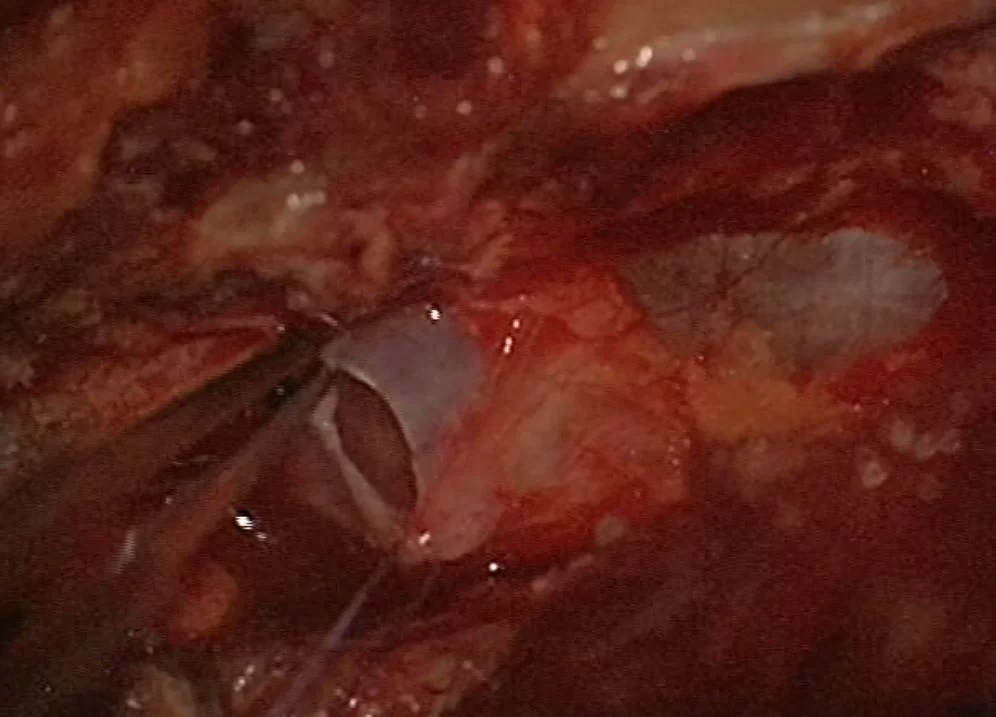

Προσωπικό αρχείο νευροχειρουργού Π. Σταυρινού

Αν τα συμπτώματα του ασθενούς ταιριάζουν με αυτά που προκαλούν οι κύστεις (κυρίως πόνος στην περιγεννητική περιοχή, πόνος στο κάθισμα και κυστικές διαταραχές) τότε αρχικά κάνω μια παρακέντηση της κύστης υπό αξονικό τομογράφο. Μ’ αυτόν τον τρόπο μειώνεται άμεσα η πίεση εντός της κύστης. Αν τα συμπτώματα του ασθενούς βελτιωθούν παροδικά, τότε προχωρώ σε χειρουργική επέμβαση. Αυτή συνήθως περιλαμβάνει διάνοιξη και θυριδοποίηση της κύστης και σύγκλιση του βαλβιδικού μηχανισμού.